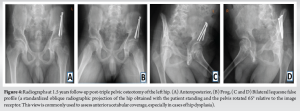

The left-sided procedure followed a similar course. At 1-year follow-up, the patient had full, painless bilateral hip motion. By 2 years post-operatively, final radiographs showed completely healed bilateral osteotomies and re-ossified femoral heads (Fig. 4).